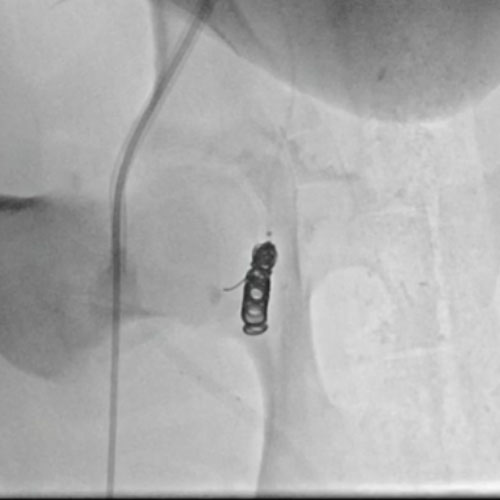

3 vs 2 Coils

Ruby Standard Coil shown  in right subclavian medial Ruby Standard Coil shown in right subclavian medial

Right Subclavian Medial

3 Ruby Standard 6x20

Embold Fibered Coil shown  in left subclavian medial Embold Fibered Coil shown in left subclavian medial

Left Subclavian Medial

2 Embold Fibered Coil 6x20